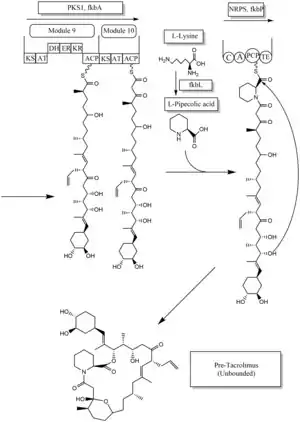

The biosynthesis of tacrolimus is hybrid synthesis of both type 1 polyketide synthases (PKS 1) and nonribosomal peptide syntheses (NRPS). The research shows the hybrid synthesis consists of ten modules of type 1 polyketide synthase and one module of nonribosomal peptide synthase. The synthetic enzymes for tacrolimus are found in 19 gene clusters named fkb. The 19 genes are fkbQ, fkbN, fkbM, fkbD, fkbA, fkbP, fkbO, fkbB, fkbC, fkbL, fkbK, fkbJ, fkbI, fkbH, fkbG, allD, allR, allK and allA.[53]

There are several possible ways of biosynthesis of tacrolimus. The fundamental units for biosynthesis are following: one molecule of 4,5-dihydroxycyclohex-1-enecarboxylic acid (DHCHC) as a starter unit, four molecules of malonyl-CoA, five molecules of methylmalonyl-CoA, one molecule of allylmalonyl-CoA as elongation units. However, two molecules of malonyl-CoA are able to be replaced by two molecules of methoxymalonyl CoA. Once two malonyl-CoA molecules are replaced, post-synthase tailoring steps are no longer required where two methoxymalonyl CoA molecules are substituted. The biosynthesis of methoxymalonyl CoA to Acyl Carrier protein is proceeded by five enzymes (fkbG, fkbH, fkbI, fkbJ, and fkbK). Allylmalonyl-CoA is also able to be replaced by propionylmalonyl-CoA.[53]

The starter unit, DHCHC from the chorismic acid is formed by fkbO enzyme and loaded onto CoA-ligase domain (CoL). Then, it proceeds to NADPH dependent reduction(ER). Three enzymes, fkbA,B,C enforce processes from the loading module to the module 10, the last step of PKS 1. fkbB enzyme is responsible of allylmalonyl-CoA synthesis or possibly propionylmalonyl-CoA at C21, which it is an unusual step of general PKS 1. As mentioned, if two methoxymalonyl CoA molecules are substituted for two malonyl-CoA molecules, they will take place in module 7 and 8 (C13 and C15), and fkbA enzyme will enforce this process. After the last step (module 10) of PKS 1, one molecule of L-pipecolic acid formed from L-lysine and catalyzed through fkbL enzyme synthesizes with the molecule from the module 10. The process of L-pipecolic acid synthesis is NRPS enforced by fkbP enzyme. After synthesizing the entire subunits, the molecule is cyclized. After the cyclization, the pre-tacrolimus molecule goes through the post-synthase tailoring steps such as oxidation and S-adenosyl methionine. Particularly fkbM enzyme is responsible of alcohol methylation targeting the alcohol of DHCHC starter unit (Carbon number 31 depicted in brown), and fkbD enzyme is responsible of C9 (depicted in green). After these tailoring steps, the tacrolimus molecule becomes biologically active.[53][54][55]